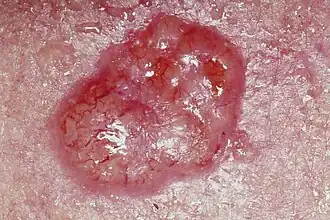

| Carcinoma basocelular em que se observa a aparência brilhante e a profusão de vasos sanguíneos . | |

Os cancros da pele (português europeu) ou cânceres de pele (português brasileiro) são cancros que se formam na pele. São causados pelo desenvolvimento de células anormais que têm a capacidade de invadir ou de se espalhar para outras partes do corpo.[10] Existem três tipos principais: carcinoma basocelular (CBC), carcinoma de células escamosas (CCE) e melanoma.[1] O conjunto dos dois primeiros, e de uma série de cancros de pele menos comuns, é conhecido como "cancros de pele não melanoma" (CPNM).[5][11] O carcinoma basocelular é de crescimento lento e pode invadir os tecidos adjacentes, mas é pouco provável que se espalhe para regiões distantes ou que provoque a morte.[5] Muitas vezes aparece como uma área de pele elevada e indolor, que se pode apresentar brilhante e com pequenos vasos sanguíneos ou na forma de uma área de pele elevada com uma úlcera.[1] O carcinoma de células escamosas apresenta maior probabilidade de se espalhar.[5] Geralmente manifesta-se na forma de um pequeno inchaço com topo escamoso, embora possa também formar uma úlcera.[12] Os melanomas são os mais agressivos. Os sinais incluem a presença de um nevo melanocítico cujo tamanho, forma e cor se alterarm, que apresenta margens irregulares, que tem mais de uma cor, que provoca prurido ou que sangra.[3]

| Carcinoma basocelular ou basalioma | Possui translucência pérola, com minúsculos vasos sanguíneos na superfície e às vezes ulceração. O mais comum (75% dos casos) e menos agressivo. Quase sempre aparece no rosto, pescoço ou braços pois são áreas altamente expostas a luz solar. Os carcinomas basocelular são originários da epiderme e dos apêndices cutâneos acima da camada basal, como os pêlos, por exemplo. Possui altos índices de cura, principalmente devido à facilidade do diagnóstico precoce.[20] | |